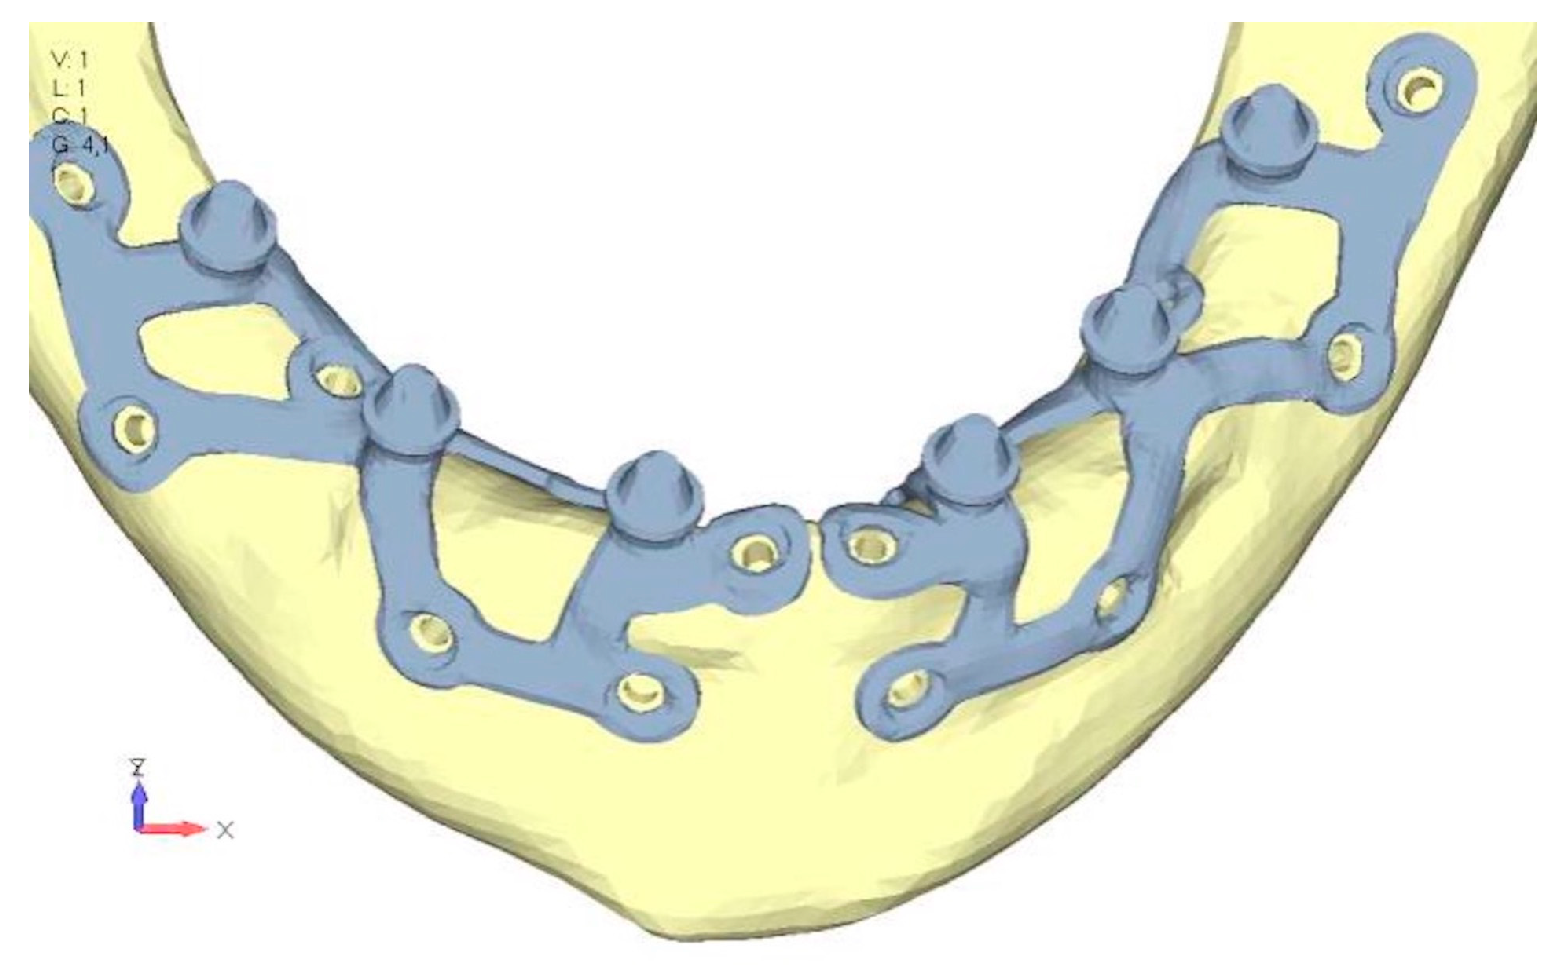

- Model V1. In this version of the implant, two anterior appendages have been added in a crestal position with the aim of better distributing the load in that area (Figure 23). The examined configuration does not result in improvements. Additionally, from a practical standpoint, it is unfeasible because the presence of the crestal screws would create an obstacle in managing the soft tissues, increasing the risk of dehiscence and exposure of the implant (Figure 24a,b).

- Model V2. The implant has been modified anteriorly by extending the anterior vestibular arms that connect to the first abutment (Figure 25). This change aims to achieve greater flexibility of the implant in that area, promoting the transmission of masticatory load to the bone through support rather than through the screws. The modification did not reveal significant changes in the stress state. The stresses near the holes are similar to those observed in model 1 (Figure 26a,b).

- Model V3. To reduce the load on the front screws, it was decided to add an additional screw, distributing the load of the anterior abutment across three screws instead of two (Figure 27). The addition of the anterior screw has certainly improved the distribution of stresses, as the volume of material experiencing stresses greater than 50 MPa near the screws has decreased (Figure 28a,b).

- Model V4. This version was derived from version 3 by adding a screw in the posterior sector, positioned in the vestibular direction (Figure 29). Again, the addition of an anchoring screw has allowed for more effective distribution of the stresses. The posterior alveolar area, particularly around the more posterior screws, remains notably stressed (Figure 30a,b). However, this phenomenon is attributed to the geometry and configuration of the bone rather than the presence of a cortical screw.